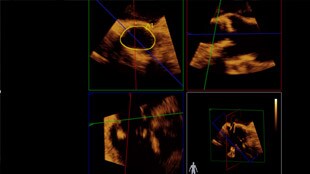

Bei Ihrer Patientin wurde eine symptomatische Aortenklappenstenose diagnostiziert. Sie ist 85 Jahre alt und leidet unter Diabetes und Bluthochdruck. Als Hochrisiko-Patientin ist sie für einen kardiochirurgischen Eingriff nicht geeignet. Jedoch ist sie möglicherweise eine Kandidatin für eine Transkatheter-Aortenklappen-Implantation (TAVI).

Der TAVI-Eingriff bietet Patienten, die keine geeigneten Kandidaten für eine offene Herzoperation sind, die Hoffnung auf eine Rückkehr zu einem aktiveren Lebensstil.